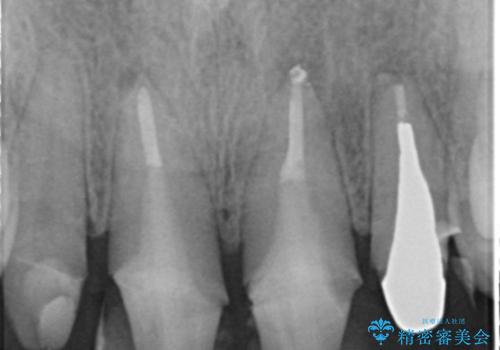

自然な前歯にしたい ジルコニアクラウンでの修復

- 前歯を綺麗にしたいとのことで来院されました。

色調・適合ともに改善するために一度被せ物を外し、歯の形を整えた後に新しい被せ物を装着していきます。

- 右上12左上12/仮歯4本+ジルコニアクラウン4本:44,000+484,000円 左上2/根管治療(保険)費用は治療当時の料金となります